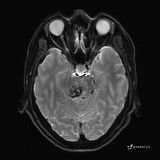

患者男,51岁。

简要病史:患者自述于1周前至某人民医院发现脑干肿瘤(具体不详),为求进一步诊断至我院就诊。

完善颅脑MRI平扫+增强,颅脑CT平扫:

ADC: